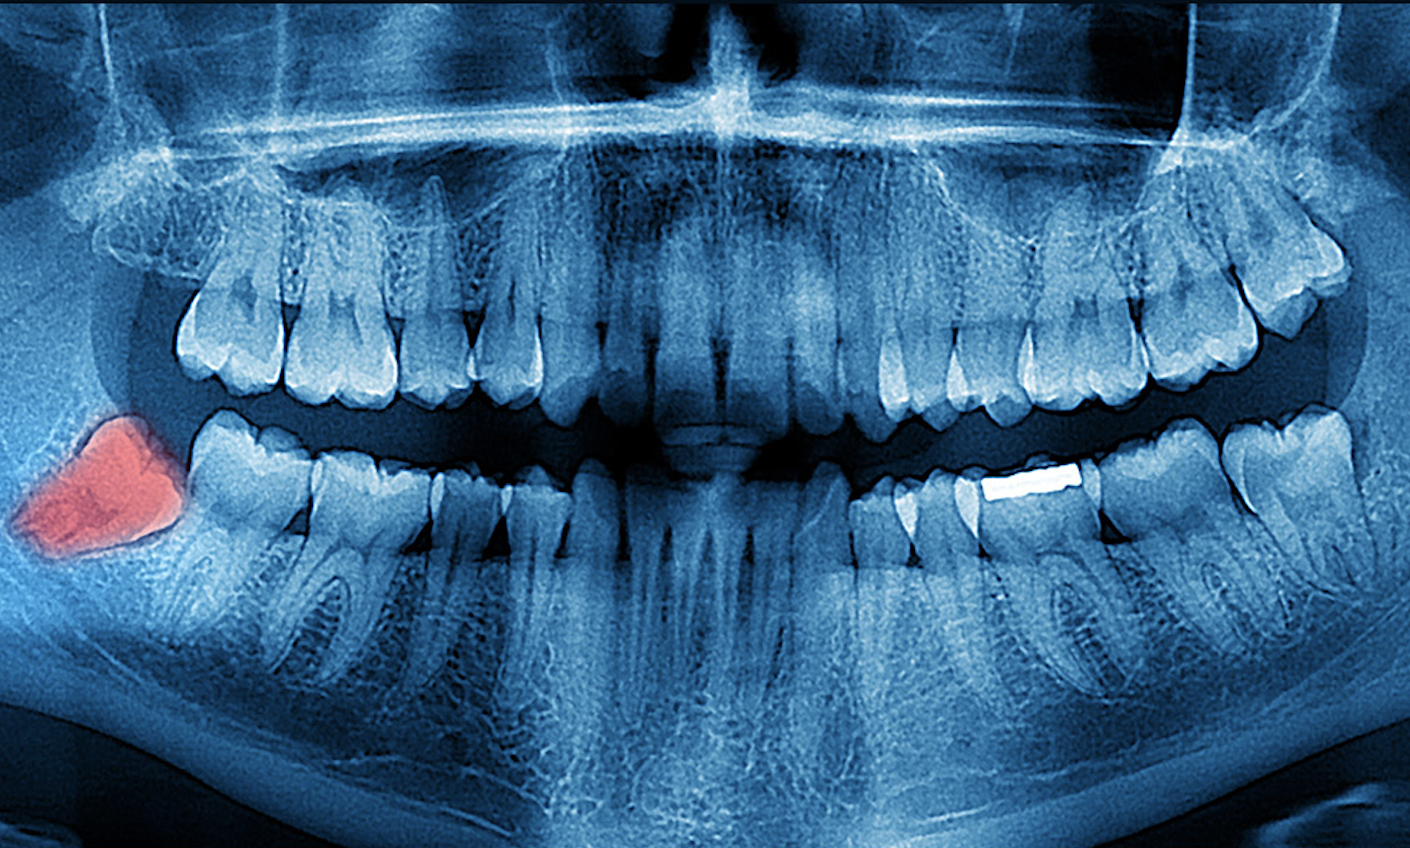

Revisión completa de tus terceros molares, encías y estructura ósea para determinar su estado actual.

Evaluación y diagnóstico preciso: analizamos y te detallamos exactamente el paso a paso de todo tu tratamiento.